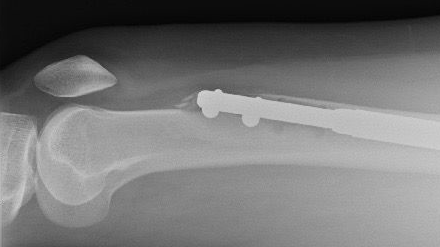

Con este procedimiento, sentir cierto dolor es esperable. Durante la operación, los huesos de las piernas se rompen en dos y una varilla de metal se posiciona adentro.

Las varillas de metal se van expandiendo gradualmente para aumentar su longitud y separar las dos mitades del hueso. El objetivo del procedimiento es aumentar la estatura del paciente. Los huesos rotos deberían volver a unirse gradualmente y llenar así el espacio que se creó entre ellos.

El clavo de la pierna izquierda le había atravesado el fémur, el hueso más fuerte del cuerpo humano. Estaba angustiada, pero dice que el doctor Guichet la calmó.

Seis semanas después, tomografías de la pierna derecha mostraron una alarmante ausencia de crecimiento óseo. Su fémur era básicamente dos pedazos de hueso unidos por una varilla de metal.

“El doctor Guichet me dijo que el clavo se había roto mientras lo sacaba”, explica. “Tenía un clavo de otro paciente que pudo insertar”.